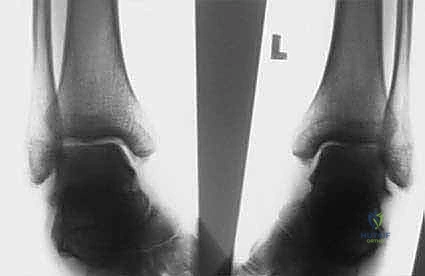

الشكل 1 • تشوهات القدم الجوفاء، منظر جانبي. لاحظ زيادة الانثناء الأخمصي لمقدمة ومنتصف القدم بالنسبة لمؤخرة القدم، وهو ما يسبب ضغطًا هائلاً على مشط القدم.

الشكل 2 • تشوهات القدم الجوفاء، منظر أمامي. يوضح مكونات انقلاب الكعب للداخل وتقوس مقدمة القدم، مما يؤدي إلى عدم استقرار الكاحل.